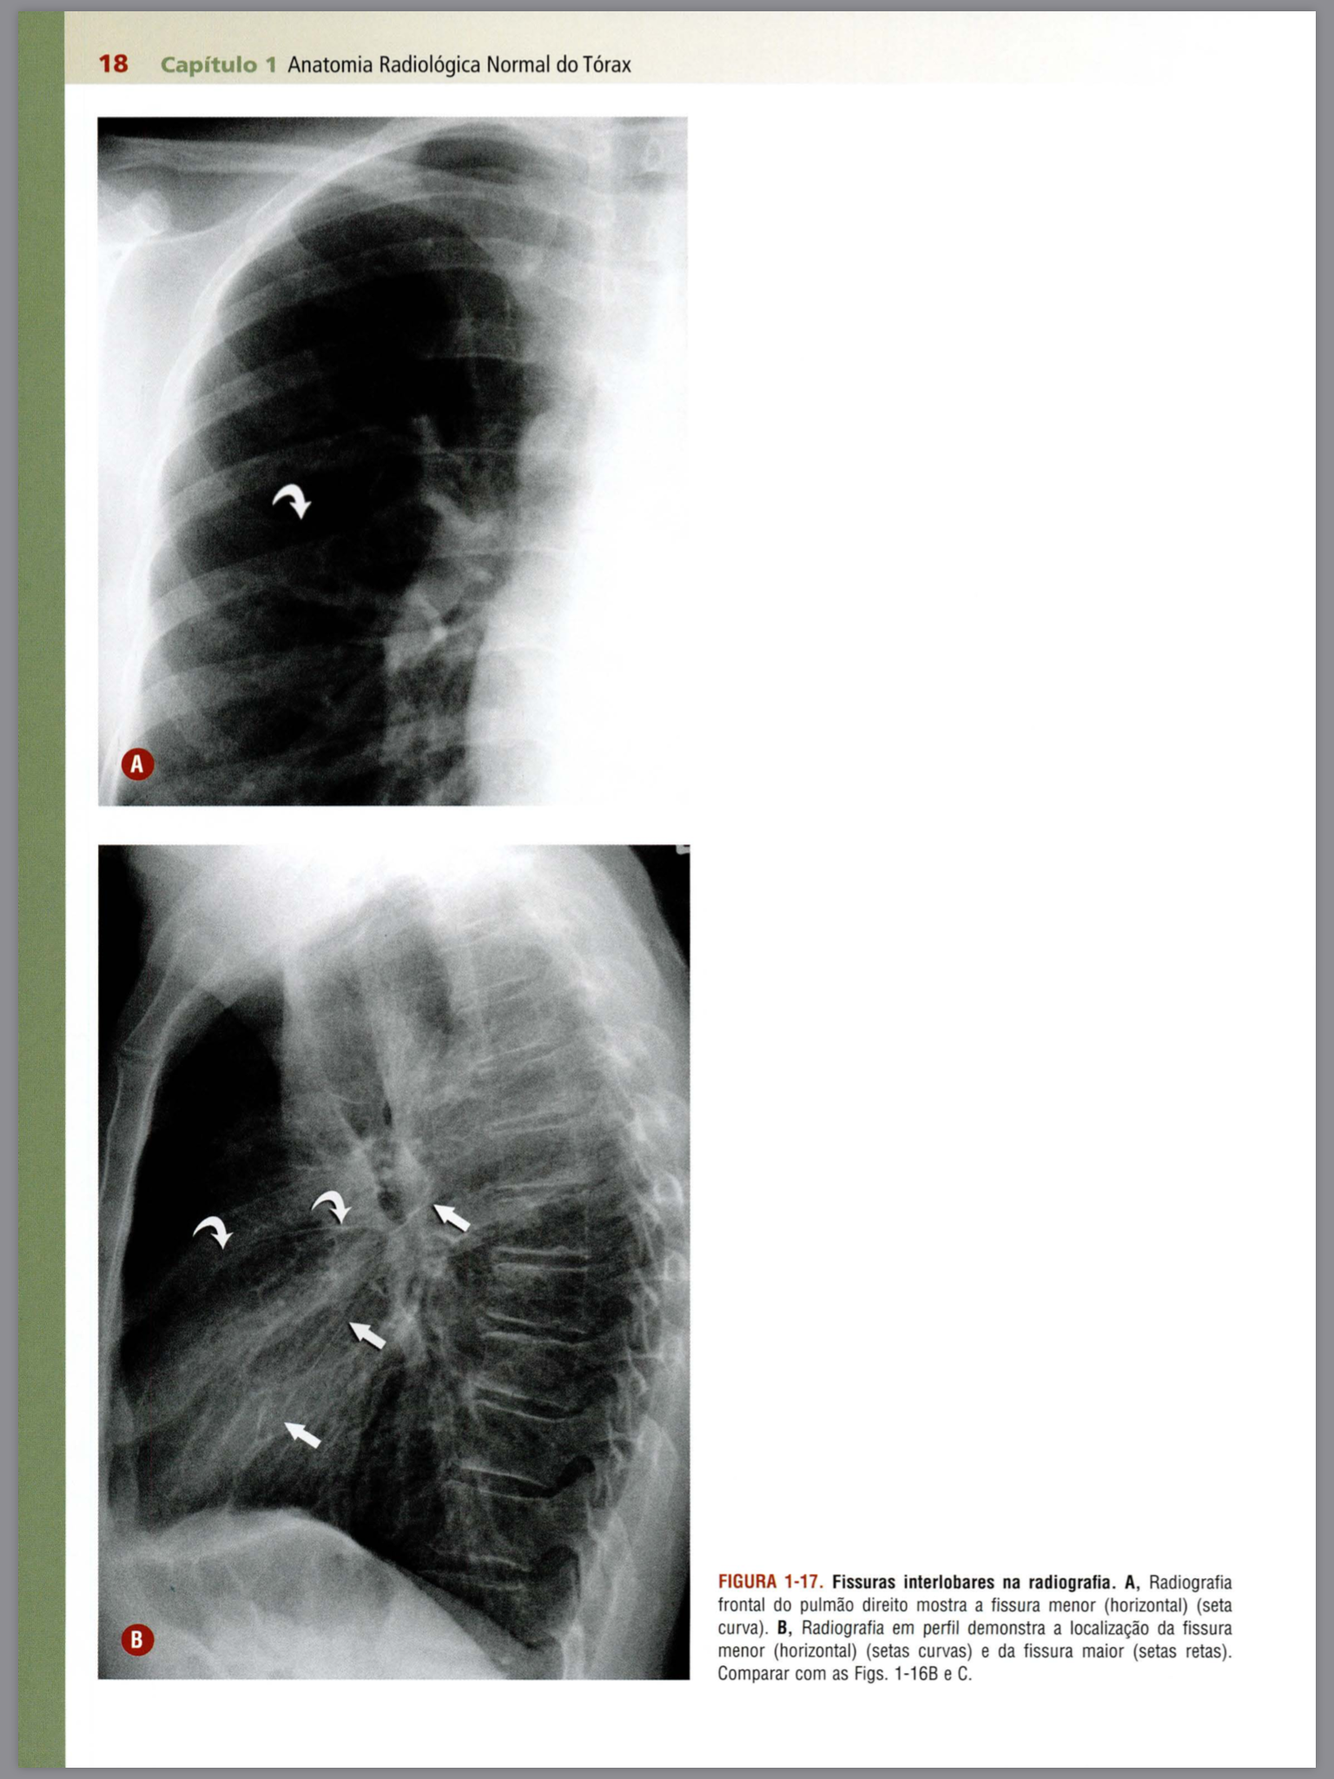

Descreva as fissuras apontadas pelas setas e os lobos pulmonares

Qual a alteração demonstrada pelas setas?

Qual estrutura apontada?